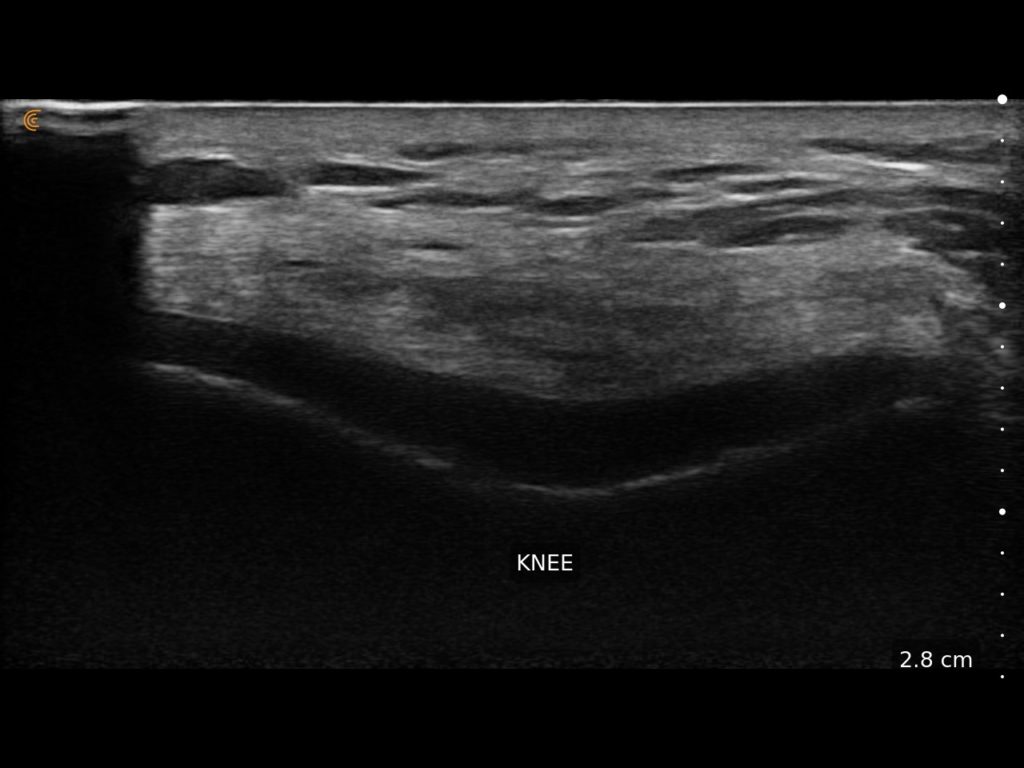

Clarius HD3 is the ideal wireless ultrasound scanner for musculoskeletal (MSK) imaging and procedural guidance. Make a confident diagnosis with high-resolution imaging of muscles, joints, ligaments, tendons, and cartilage both at rest and in motion.

What I like about Clarius is that it is an excellent ultrasound that allows me to have versatility, quality and precision.